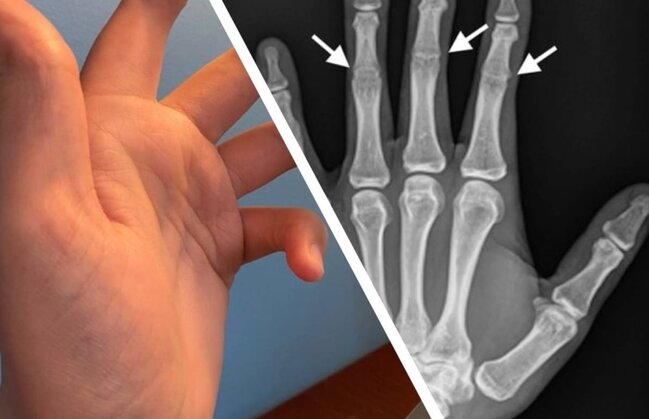

Bu adamın əlində orta oynaqlar YOXDUR - FOTO

Bu adamın əlində orta oynaqlar YOXDUR - FOTOBarmaqlarınızda orta oynaqlar olmadan özünüzü təsəvvür edə bilərsiniz? Həyatınızın nə dərəcədə çətinləşəcəyini anlatmağa ehtiyac yoxdur. Barmaqlar bükülmədən heç yazı yazmaq belə, mümkün deyil.

Bu adamın əlində orta oynaqlar YOXDUR - FOTOQeyd edək ki, sümük inkişafına təsir edən bu nadir irsi xəstəlik simfalangizm adlanır.